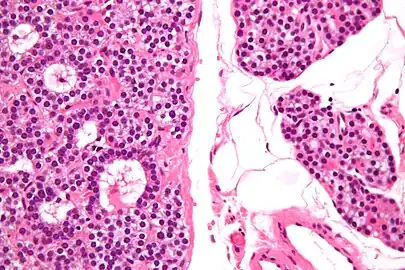

Micrograph of a parathyroid adenoma (left) and normal parathyroid gland (right). H&E stain.

Normal parathyroid gland with prominent adipose tissue is seen on the right of the image.-High magnification

Intermediate magnification